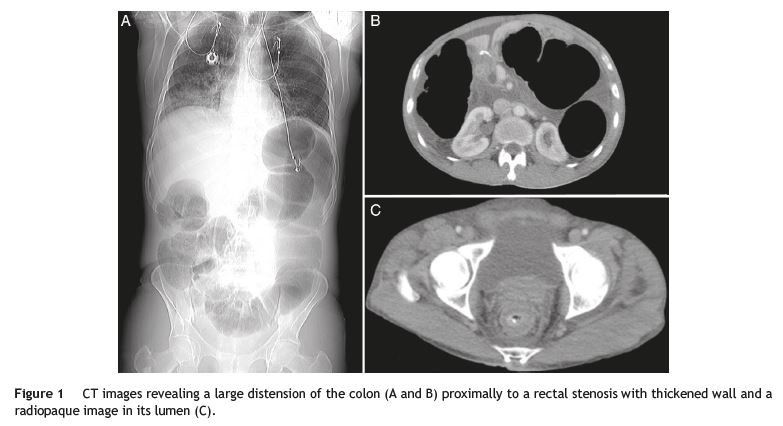

A 51-year-old man presented with a 1-day history of intense abdominal pain, vomiting, constipation and inability to pass gas. His past medical condition comprised an advanced gastric SRC (T3N2M0), diagnosed when the patient was 47 years old. He was submitted to distal gastrectomy and adjuvant chemotherapy and three years later, palliative chemoradiotherapy for non-obstructive rectal and prostate metastasis. Physical examination revealed no signs of peritoneal irritation. Laboratory tests showed an acute kidney injury. An abdominal X-ray demonstrated marked colonic distension and computed tomography (CT) revealed a malignant rectal stenosis with proximal colonic dilation (Fig. 1A-C). Considering his medical condition, the patient was referred for palliative stenting and underwent a sigmoidoscopy. The sigmoidoscopy depicted a malignant stricture with an impacted chicken bone leading to edema and complete obstruction (Fig. 2A). After removal of the foreign body with a rat-tooth forceps (Fig. 2B and C), the colonoscope was easily passed beyond the stricture (Fig. 2D). Due to reestablishment of bowel movements, stenting was postponed. Upon CT review, a radiopaque object was found within the rectal stricture (Fig. 1C).